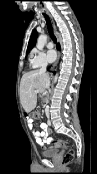

In order to investigate the performance of our method on high-resolution 3D data, we measured the average runtime over 986 registrations on a dataset of follow-up thorax abdomen CT scans provided by the Radboud University Medical Center, Nijmegen, Netherlands. The images have resolutions in the range of . As full image resolution was slightly out of reach due to memory restrictions of the GPU, we evaluated our approach on half, quarter, eighth and sixteenth resolution per dimension.

For the highest resolution, average runtime was seconds, with an average speedup of compared to the CPU-based parallel OMP implementation (Table 1). On the lower resolutions, our method achieves sub-second runtimes at a speedup of about one order of magnitude. A majority of the runtime on the lower resolutions is spent on the multi-level creation, due to the large memory transfer and downsampling.

It is prudent to ask whether moving from double precision to single precision on the GPU introduces differences due to rounding. In fact, we observed that this can have an effect (Figure 1). However, it typically only occurs when there are no clear correspondences, such as in regions of the colon with different content, or when the examination table is visible in one of the two scans. In these areas, there is no strong objective function gradient in either direction during optimization, so that numerical differences have a larger impact. However, we argue that if such areas were to be registered accurately, a more elaborate model that accounts for the possible removal of structures would have to be employed in any case.